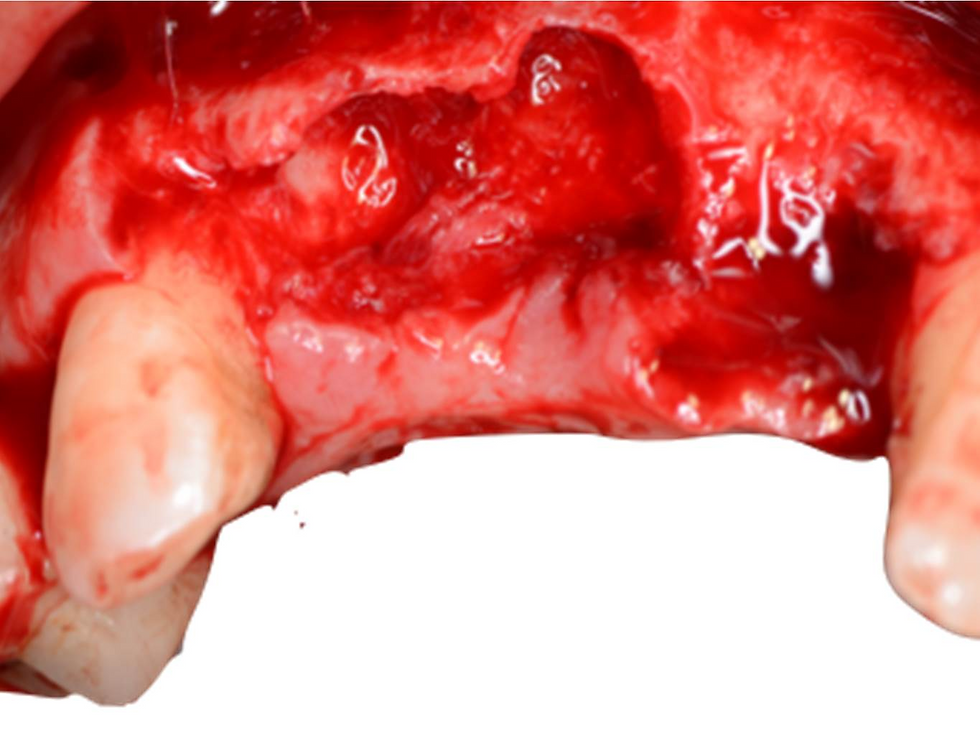

The site exposed by rising a trapezoidal flap

Frontal view of the bone defect.

Occlusal view of the bone defect.

Perforation of the cortical plate of the bone to allow the defect volume to be populated with new vessels.